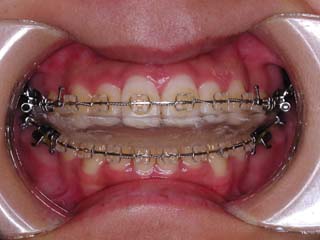

主訴:顎が歪んでいる 下顎が出ている

診断名:骨格性下顎左方偏位を伴う骨格性下顎前突

年齢:28歳

使用した主な装置名:TPB、マルチブラケット装置

抜歯/非抜歯および抜歯部位:抜歯(上顎左右第一小臼歯)

治療期間:動的処置2年3か月、経過観察3年

費用の目安:保険適応 自己負担金として30~50万

リスク、副作用:外科手術によるリスク、マルチブラケット治療に伴う歯根吸収など偶発症が発生するリスクがある。

強い下顎前突と下顎の左方変位がみられます。成長を終了した永久歯列ですので、骨の大きさのズレへのアプローチは大きく別れる所です。程度が小さければ、歯の傾きで補うように解決しますし、大きなズレであれば、外科的に骨のズレを改善する治療が選択されます。前後のズレ、左右のズレと条件が重なってきた場合、より外科矯正での改善が望ましいものとなるでしょう。

一般的な外科矯正治療の流れは、術前矯正・外科矯正・術後矯正・保定治療と移行します。術前矯正では、手術を行う時点で、上下がぴったり合うような歯列に仕上げる事になりますので、逆に言えば、手術をしていない直前においては、とんでもなく噛めない状態となっている事が多いです。このケースでは下顎のみのセットバック(後退術)をSSROにて行いました。